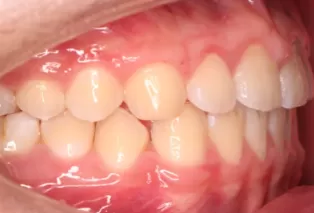

Photos intra-orales